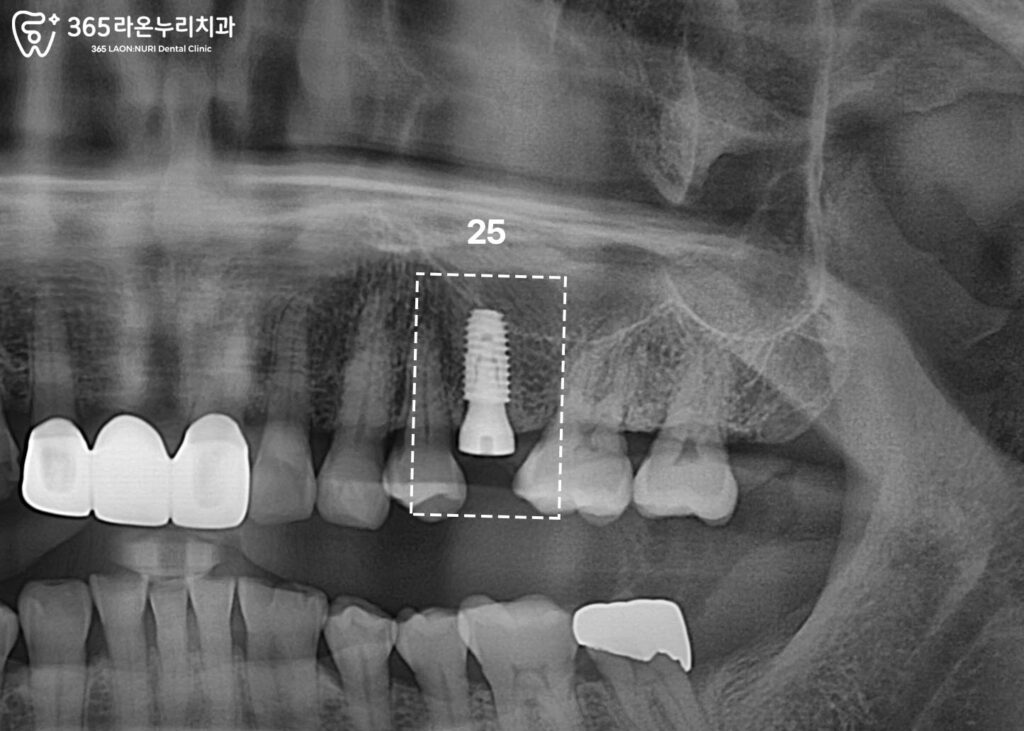

임플란트 픽스처 식립

뼈의 양과 질, 상악동의 위치를 확인한 후

계획한 직경과 길이의 픽스처를 심습니다.

픽스처와 뼈가 잘 붙어야

이후에 씌우는 보철을

오래 사용할 수 있습니다.

따라서 수술 후에는

일정한 치유 기간과 관리가 필요합니다.

상악은 보통 4-6개월,

하악은 2-4개월 정도의

회복 기간이 가집니다.